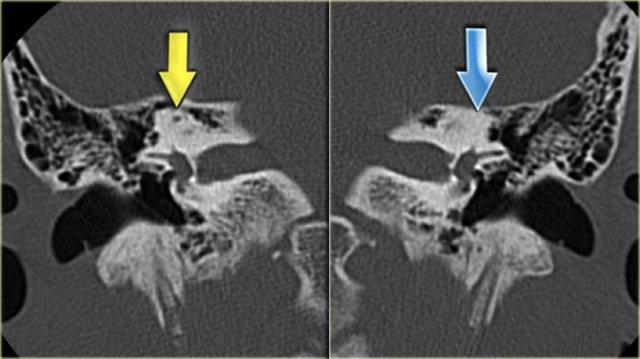

Hình ảnh bên trái của bệnh nhân nam 14 tuổi với điếc tiếp nhận hai bên.

Vôi hóa ống bán khuyên trên bên trái (mũi tên vàng).

Tai phải để so sánh (mũi tên xanh lam).

Hình ảnh mặt phẳng coronal của cùng bệnh nhân trên.